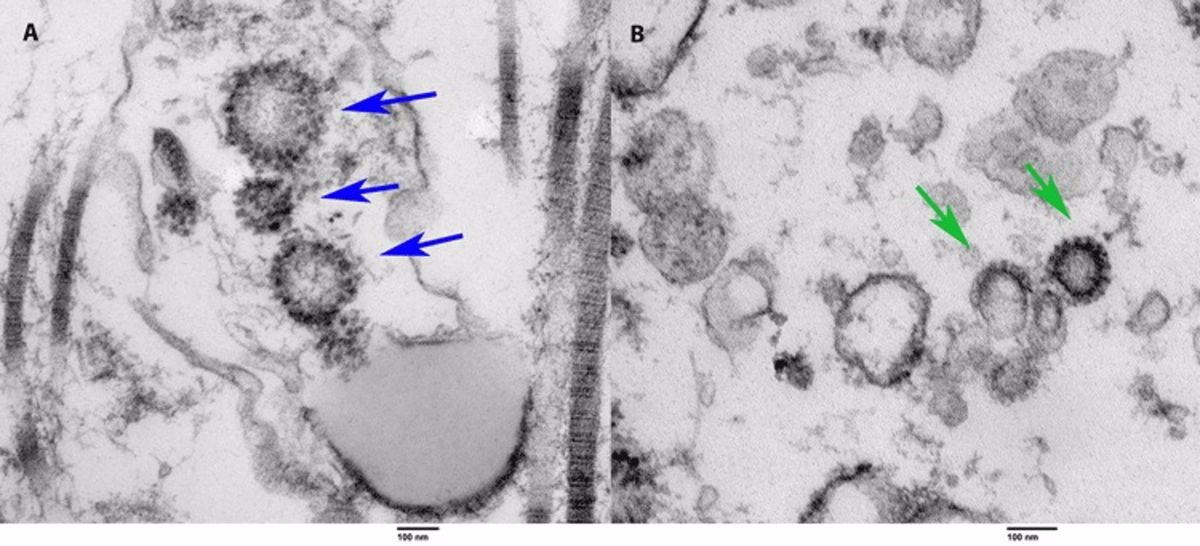

Los investigadores analizaron el tejido testicular de las autopsias de seis hombres que murieron de la infección por COVID-19. Encontraron alteraciones en la función espermática en tres de las muestras de testículos y evidencia del virus usando microscopía electrónica en el tejido de uno de ellos.

"También identificamos la presencia del virus en un hombre que se sometió a una biopsia de testículo para la infertilidad, pero que tenía antecedentes de COVID-19. Así que el paciente dio negativo y estaba asintomático después de tener COVID-19 pero aún así mostraba la presencia del virus dentro de los testículos. Esta es la primera investigación publicada que informa sobre el caso de un paciente vivo que se recuperó del virus con presencia de COVID-19. El hallazgo es novedoso, notable, y ciertamente digno de una mayor exploración", apunta Ramasamy.